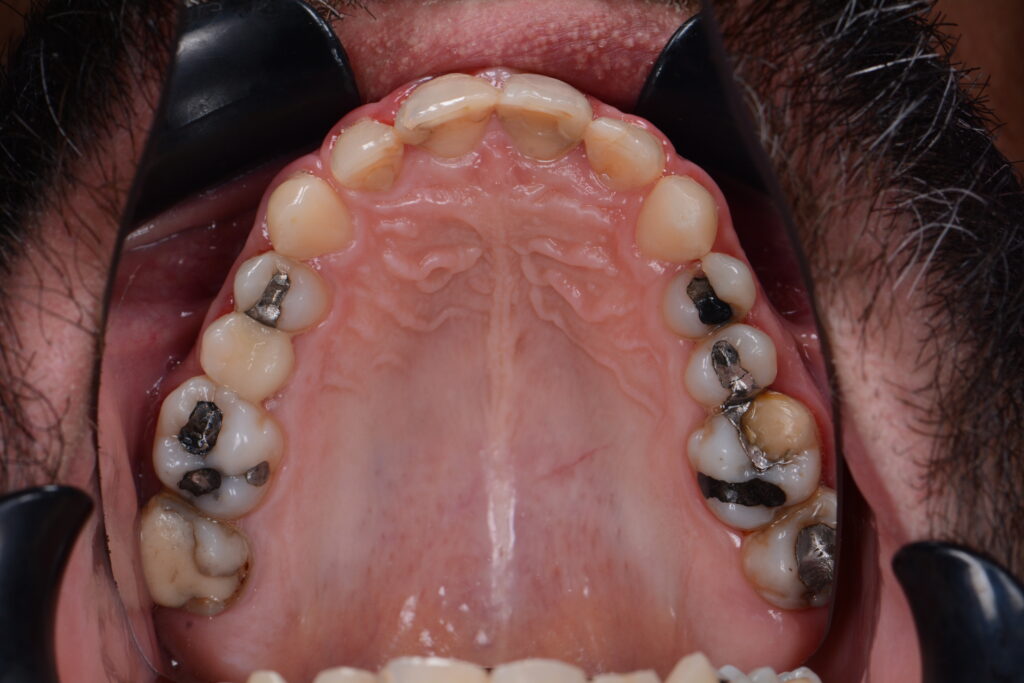

Früher wurden im Seitenzahnbereich sehr häufig Amalgamfüllungen verwendet. Diese metallfarbenen Zahnfüllungen sehen nicht nur wenig ästhetisch aus, sie setzen auch Quecksilber frei und sind damit eine potentielle Gesundheitsgefahr. Wenn Sie Ihre alten Amalgamfüllungen entfernen lassen möchten, kommen Kunststofffüllungen als weitgehend unbedenklicher Ersatz infrage.

Möchten Sie noch mehr Fotos Fotos von Kompositfüllungen sehen? Folgen Sie Dr. Azzawi auf Instagram: